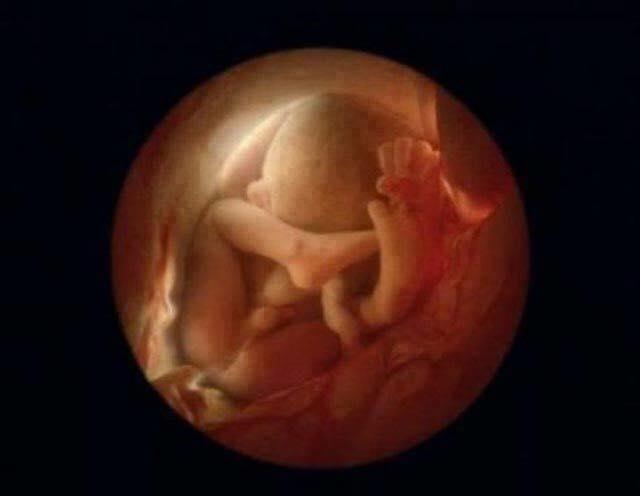

6 meses, se encaixando de cabeça para baixo